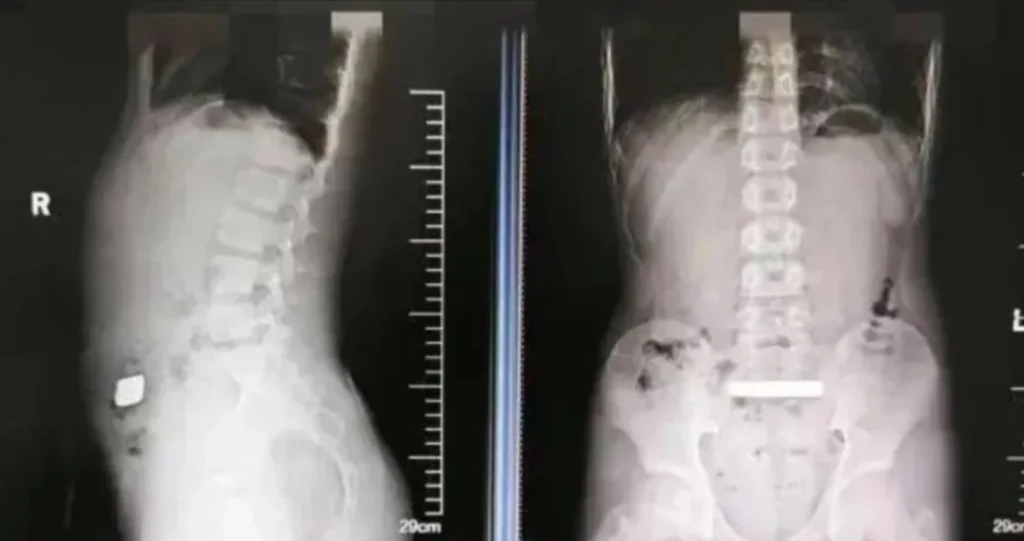

इससे चिंतित होकर उसके माता-पिता उसे तुरंत डॉक्टर्स को दिखाने के लिए सूज़ौ विश्वविद्यालय, चीन (China News) में लाए थे। डॉक्टर्स ने एक्स-रे परीक्षणों से पता लगाया कि लड़के की आंत में एक सोने धातु की वस्तु फंसी हुई है। शुरू में डॉक्टरों ने इस पर विचार किया क्योंकि लड़के में गंभीर लक्षण नहीं दिखे।

लेकिन दो दिनों तक कोई सकारात्मक परिणाम नहीं आने के बाद स्कैन से पता चला कि बार हिली नहीं थी। और जोखिम के बढ़ने के साथ चीनी (China News) डॉक्टर तुरंत हरकत में आ गए। हालांकि दो दिनों तक कोई समाधान नहीं होने के बाद एक्स-रे ने पुष्टि की, कि सोने की वस्तु उसके शरीर के भीतर स्थिर थी। डॉक्टरों ने एक्स-रे किए जिसमें बच्चे की आंतों में एक घनी धातु की वस्तु फंसी हुई दिखाई दी।